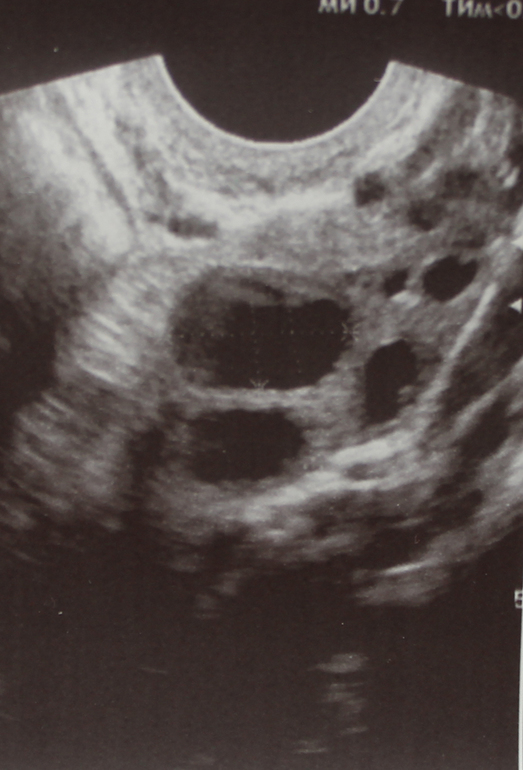

ФолликулометрияДевочки, кто разбирается, что это за образование на 6 дц? см. фото

Размер 17х11 мм (это на 6 дц, поэтому понятно не может быть ДФ при моем цикле в 30 дней и о. на 15 дц обычно). УЗИстка просто написала, что это максимальный фолликул. И даже никак не прокомментировала, я уже потом в протоколе узи прочла.

а еще рядом с ним еще один фолик - этот может быть доминантным?